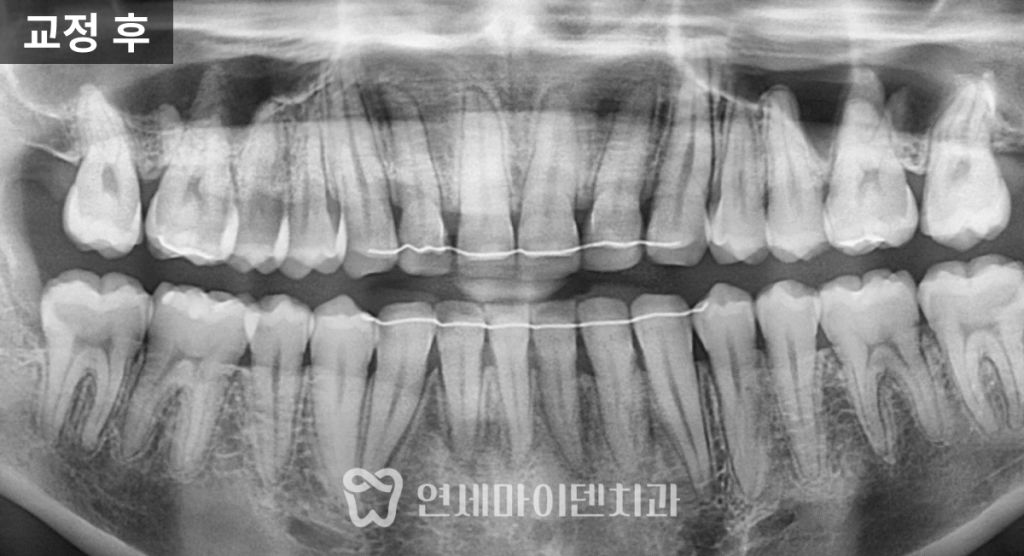

파노라마 방사선에서도

치근 흡수나 잇몸 손상 없이

안정적으로 마무리되었습니다.

다행히 전반적인 치근 상태는

양호한 편이었습니다.